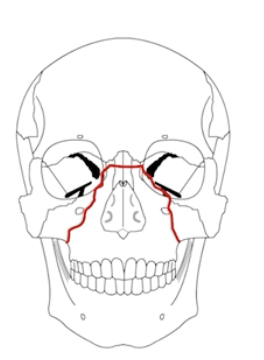

What is a LeFort 1 Fracture?

Transverse fracture separating the maxilla from the pterygoid plate and nasal septum.

(palate is mobile)

What is a LeFort 2 fracture?

Pyramidal fracture through the maxilla, orbital tib, nasal bridge, and hard palate

(nose and mouth mobile)

What is a lefort 3/4 fracture?

Lefort 3: Fracture through frontozygomatic sutures, orbits, nose, and ethmoids (face separated from skull)

Lefort 4: 3+frontal bone involvement